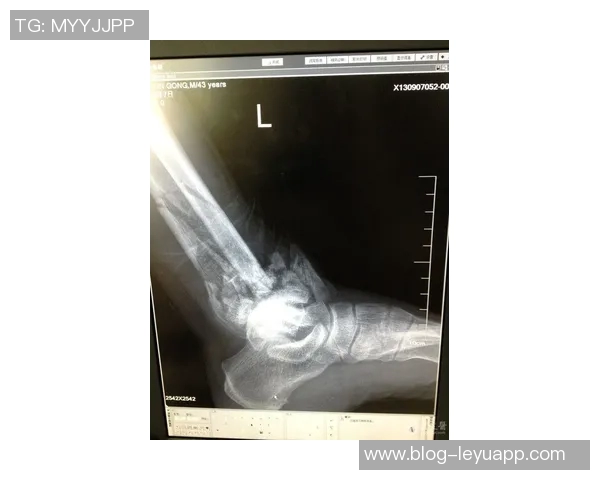

黄威作为广西平果队的重要成员,他的伤情引起了广泛关注。据医疗团队的初步诊断,黄威右侧胫腓骨发生了骨皮质断裂,这种类型的损伤通常伴随着剧烈疼痛和周边组织的损伤。进一步检查显示,该部位不仅存在骨折,还可能涉及软组织损伤,这给他的恢复增加了难度。

根据医学专业人士的解释,胫腓骨作为下肢的重要承重骨骼,其损伤会直接影响到运动员的行走、跑动以及跳跃能力。这种情况下,需要经过必要的影像学检查如X光或CT扫描,以确定具体损伤程度和范围。同时,也需要密切关注血液循环及神经功能,以防止并发症出现。